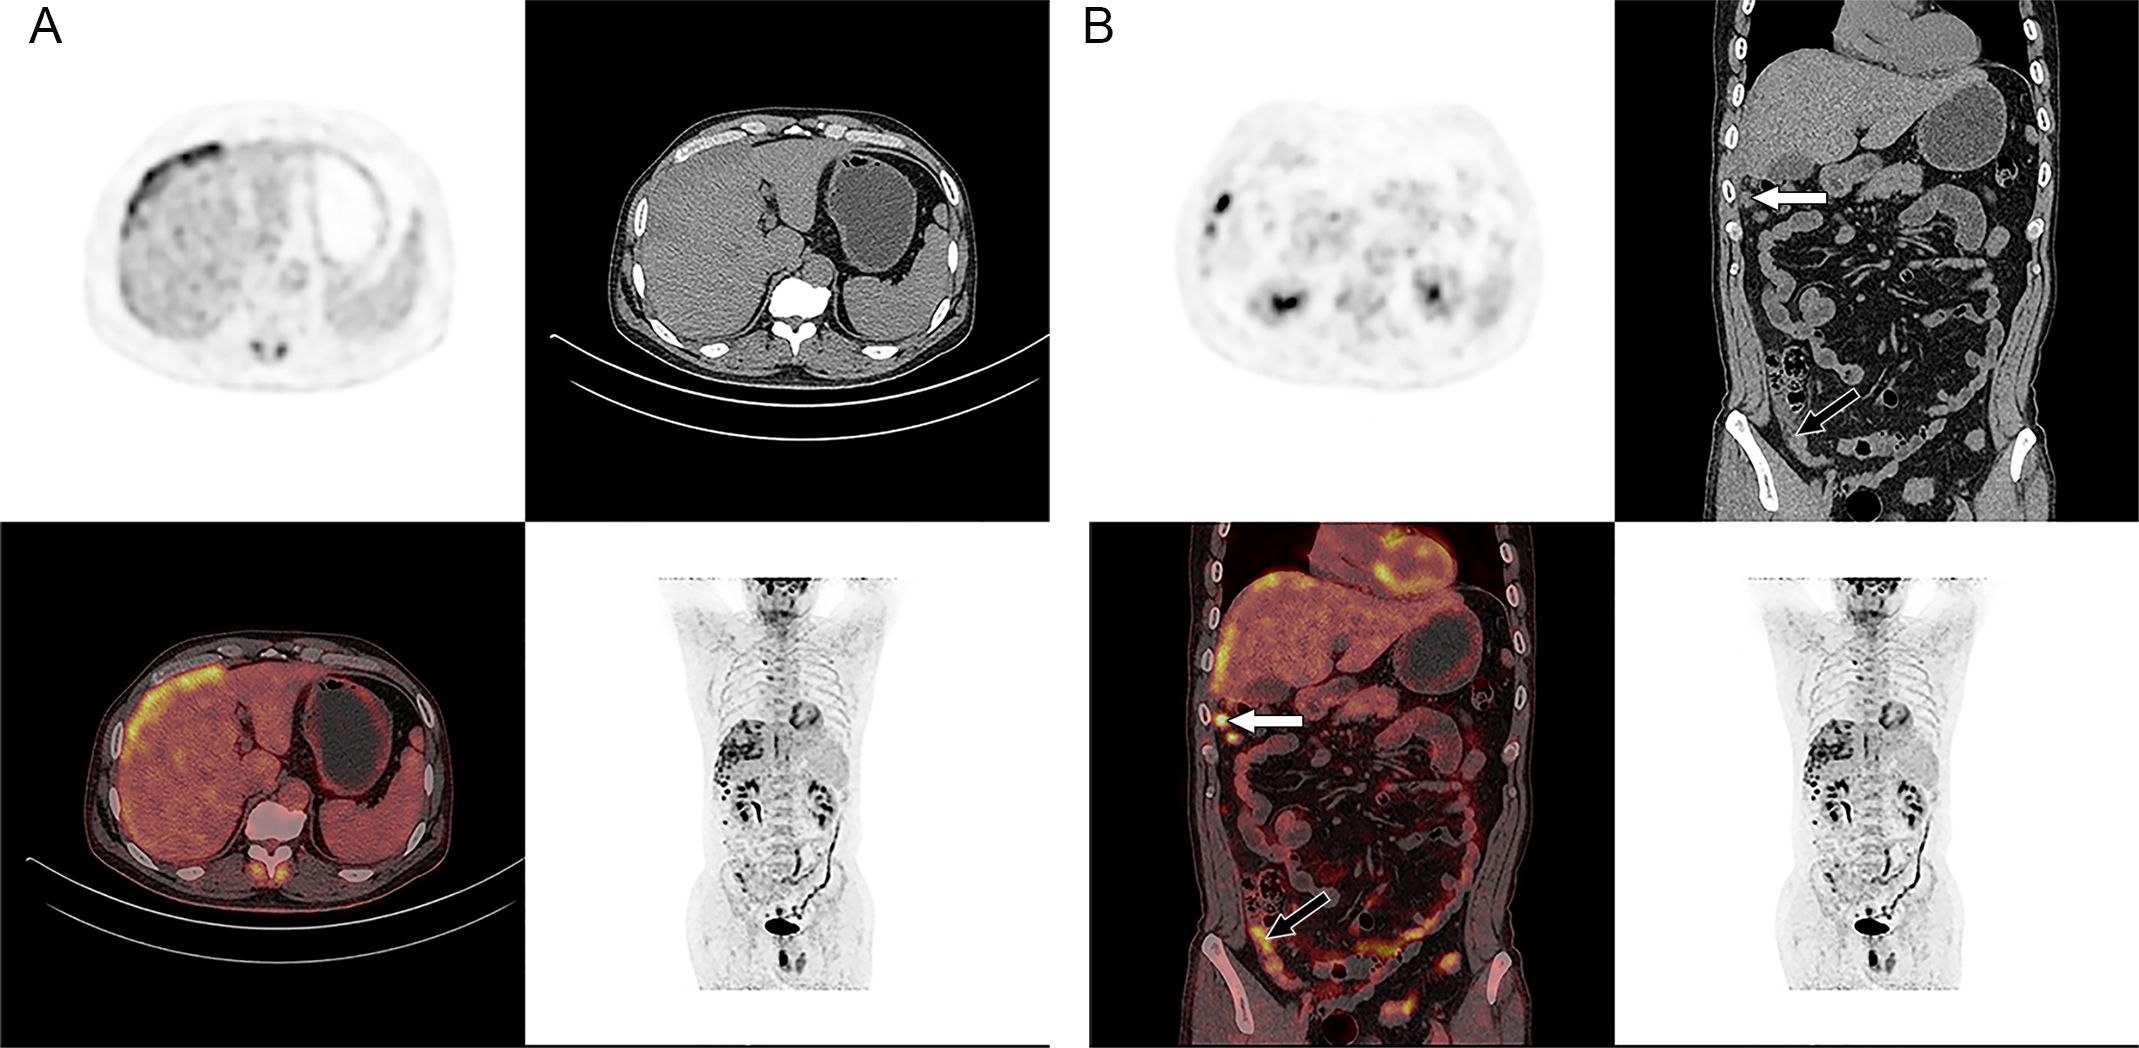

Figure 3

18F-FDG PET/CT images of the whole body. Axial PET/CT images of the abdomen showed abnormally elevated FDG activity in the multiple ill-defined low-attenuation lesions of the right subdiaphragm and right anterior and left medial lobe of the liver (SUVmax of 11.2 and SUVmax of 12.6 in late phase) (A). Coronal PET/CT images of the whole body showed abnormal uptake in the right peritoneum with irregular nodular thickness (black arrow) (SUVmax of 7.7 and SUVmax of 9.3 in late phase) and multiple high activity nodules in the right abdominal cavity (white arrow) (the largest one is SUVmax of 11.9 and SUVmax of 11.6 in late phase) (B).

Ultrasound (US) imaging revealed an ill-defined, heterogeneous, hypoechoic lesion involving the right subdiaphragm as well as the right anterior and left medial lobes of the liver. The hepatic parenchyma showed diffuse heterogeneity without distinct nodules. Thoracic computed tomography (CT) scans demonstrated an elevated right diaphragm, bilateral pleural thickening, and bilateral diaphragmatic pleural calcifications, along with enlarged anterior mediastinal lymph nodes. No significant pulmonary masses were identified. Abdominal contrast-enhanced CT images in the late arterial phase revealed multiple nodular and sheet-like low-attenuation lesions with peripheral enhancement in the right subdiaphragm, right anterior, and left medial lobes of the liver (Figure 1). These lesions showed “washout” in the portal vein and late phases. Enhanced nodules were observed in the peritoneum around the liver and in the fat septa of the ascending colon. Based on thoracic CT findings, the common primary malignancies were excluded, including masses in the lung, pancreas, spleen, kidneys, ureters, and prostate. Magnetic resonance (MR) imaging indicated intermediate-to-low intensity lesions on T1-weighted images (T1WI) and central intermediate-to-low intensity with peripheral intermediate-to-high signal intensity on T2-weighted images (T2WI). Diffusion-weighted imaging revealed restricted diffusion (Figure 2). No significant retroperitoneal abnormalities were noted. An 18-fluorodeoxy-glucose positron emission tomography with CT (18F-FDG PET/CT) scan revealed abnormally elevated FDG uptake in the poorly defined low-attenuation lesions in the right subdiaphragm and right anterior and left medial lobes of the liver, with a maximum standardized uptake value (SUVmax) of 11.2. Additional FDG activity was noted in the right peritoneum with irregular nodular thickening (SUVmax 7.7) and multiple hypermetabolic nodules in the right abdominal cavity, the largest of which had an SUVmax of 11.9 (Figure 3). No abnormal FDG uptake was observed in the lungs. An ultrasound-guided biopsy of the right subdiaphragmatic lesion and hepatic mass revealed dense fibrocollarous tissue invasion by atypic tumoral cells with spindle, triangular, or polygonal-shaped and hyperchromatic nuclei, involving both the peritoneum and liver (Figure 4). Immunohistochemical analysis showed these cells were positive for Ki-67 (20%), cytokeratin (CK) 7, WT-1, vimentin, CK (pan), D2-40 (weakly positive), and calretinin (CR), but negative for villin, CK20, and CDX-2. These findings supported a diagnosis of desmoplastic malignant peritoneal mesothelioma (DMPM). The patient underwent chemotherapy with pemetrexed and cisplatin and was discharged after completing the treatment.